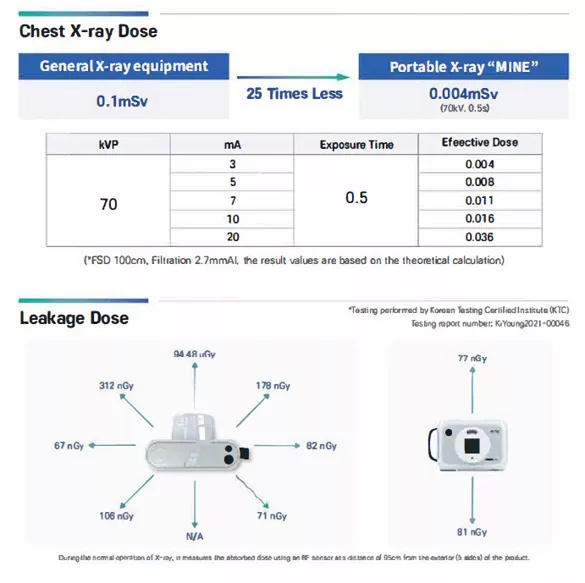

AI-Driven Accuracy and Uncompromising Safety

The device is equipped with built-in AI image enhancement software, providing clinicians with unprecedented clarity. Simultaneously, safety remains a core priority in the system’s development. The Nooka includes a safe-distance sensor and specialized filters for pregnancy and pediatric care. Finally, the device is FDA-approved and has undergone rigorous safety testing for three years, ensuring it meets the highest international medical standards.

- Safety First: Features a safe-distance sensor, radiation filters for kids/pregnancy, and outdoor-use approval (Korea).

- Versatile Power: Operates at 40–80 kV / 3 mA, suitable for orthopedics, sports medicine, podiatry, and veterinary use.

- Voltage/Current: 40–80 kV / 3 mA

- Safety: Safe-distance sensor, kid/pregnancy filters, outdoor-approved